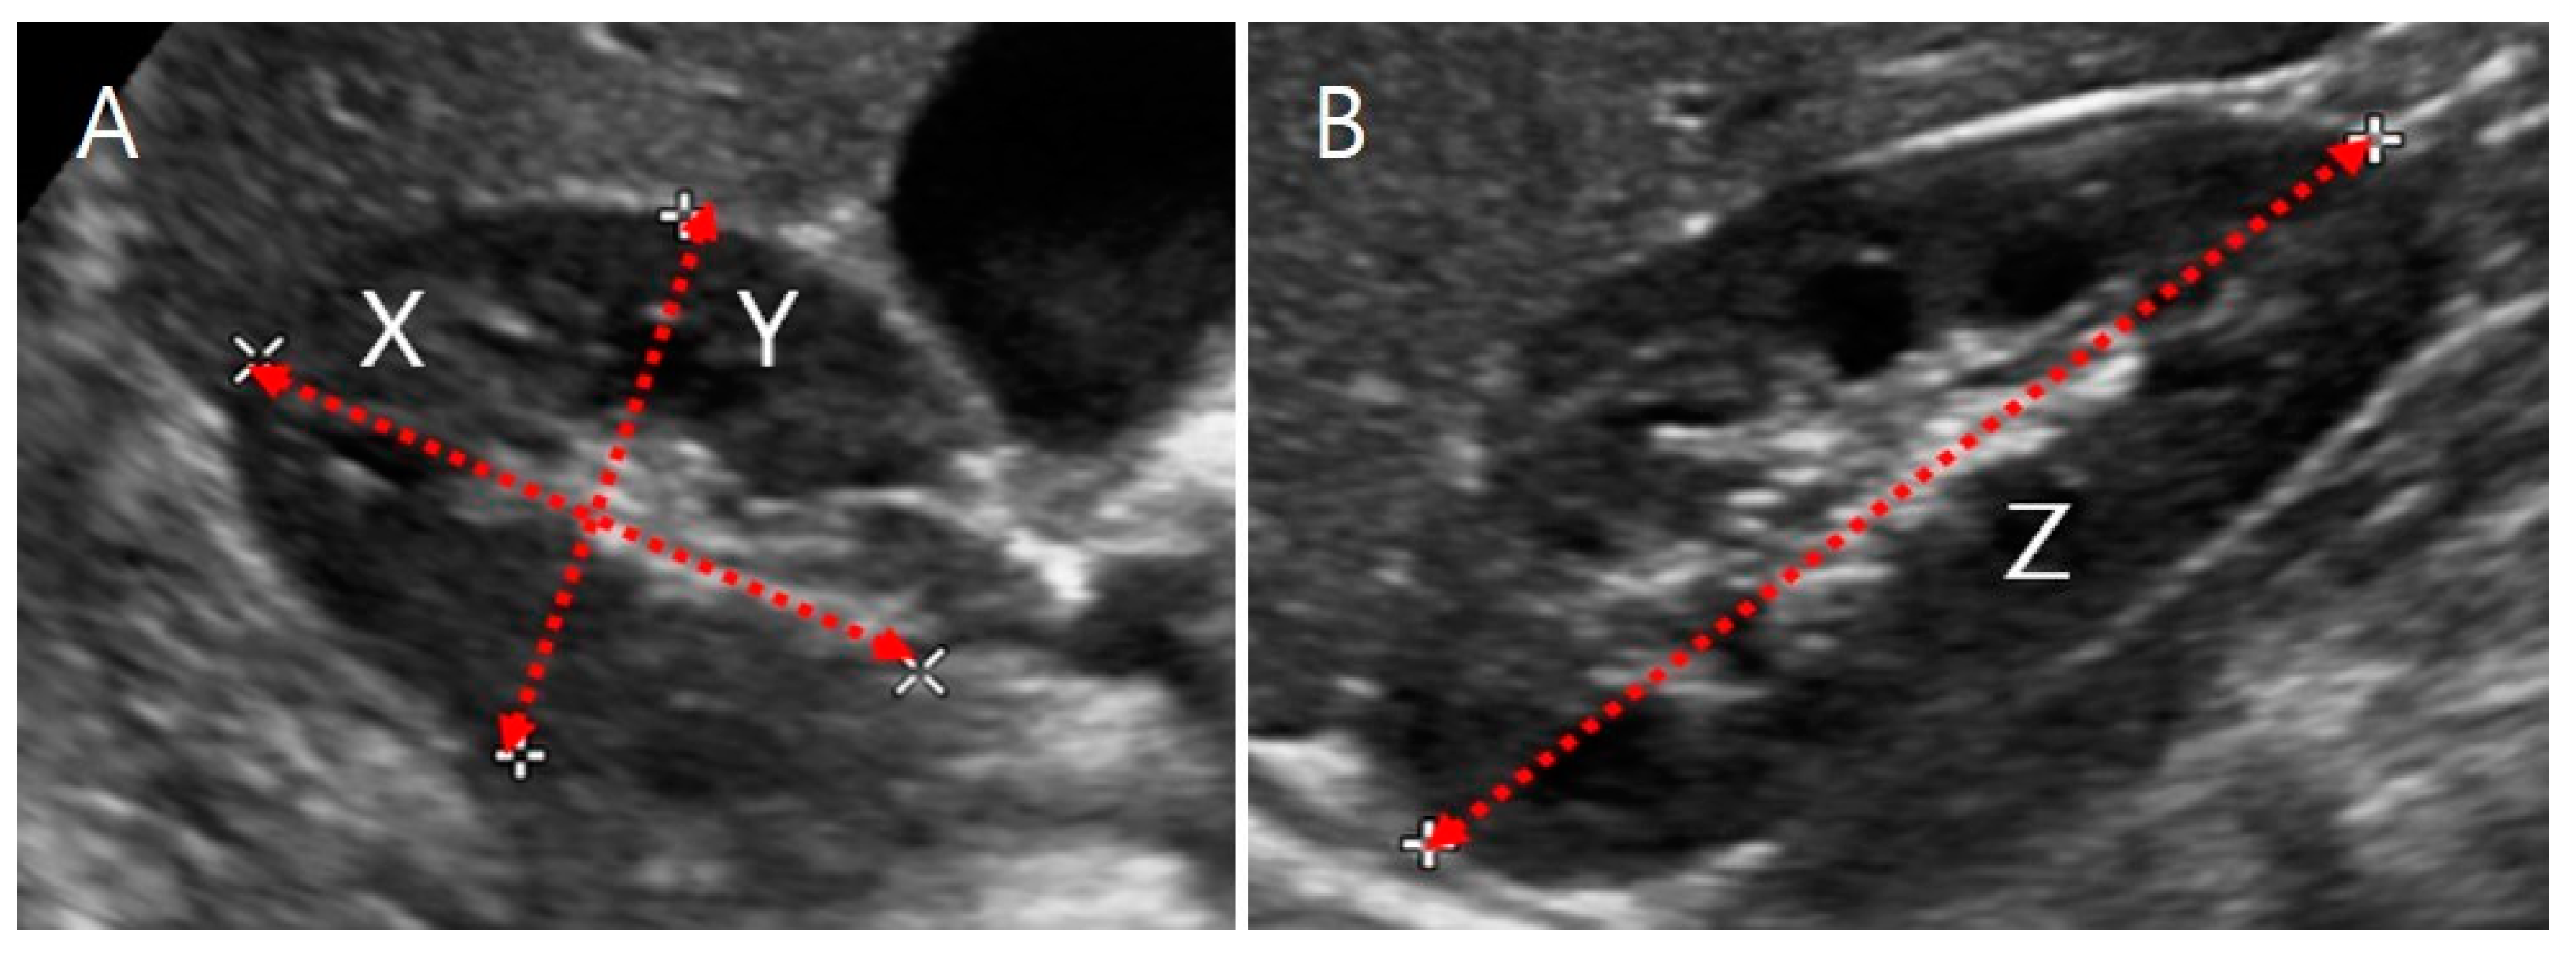

2.3.1. US Images and Ellipsoidal Method

2.3.2. US Images and Image Processing Program